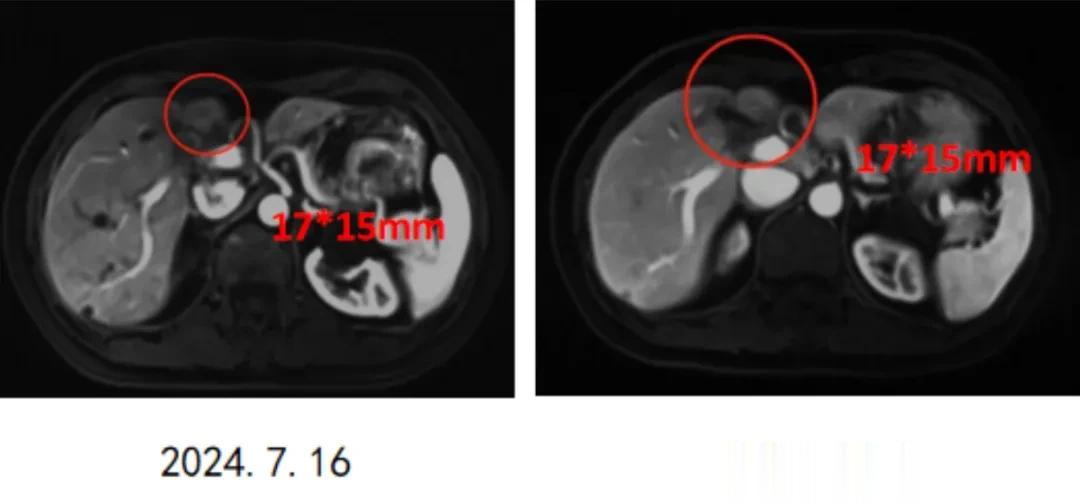

于是2024年9月11日,罗女士进入vNKT细胞治疗,细胞回输后仅1个月,罗女士就因担心病灶继续扩大而提前复查,结果影像学惊喜看到17*15mm的病灶稳定住了,没有继续进展,这也坚定了她的治疗信心。

直至2025年10月末次随访,罗女士经过11个疗程的序贯个体化vNKT免疫细胞治疗,病情已经彻底稳定下来,她也顺利通关术后2年。